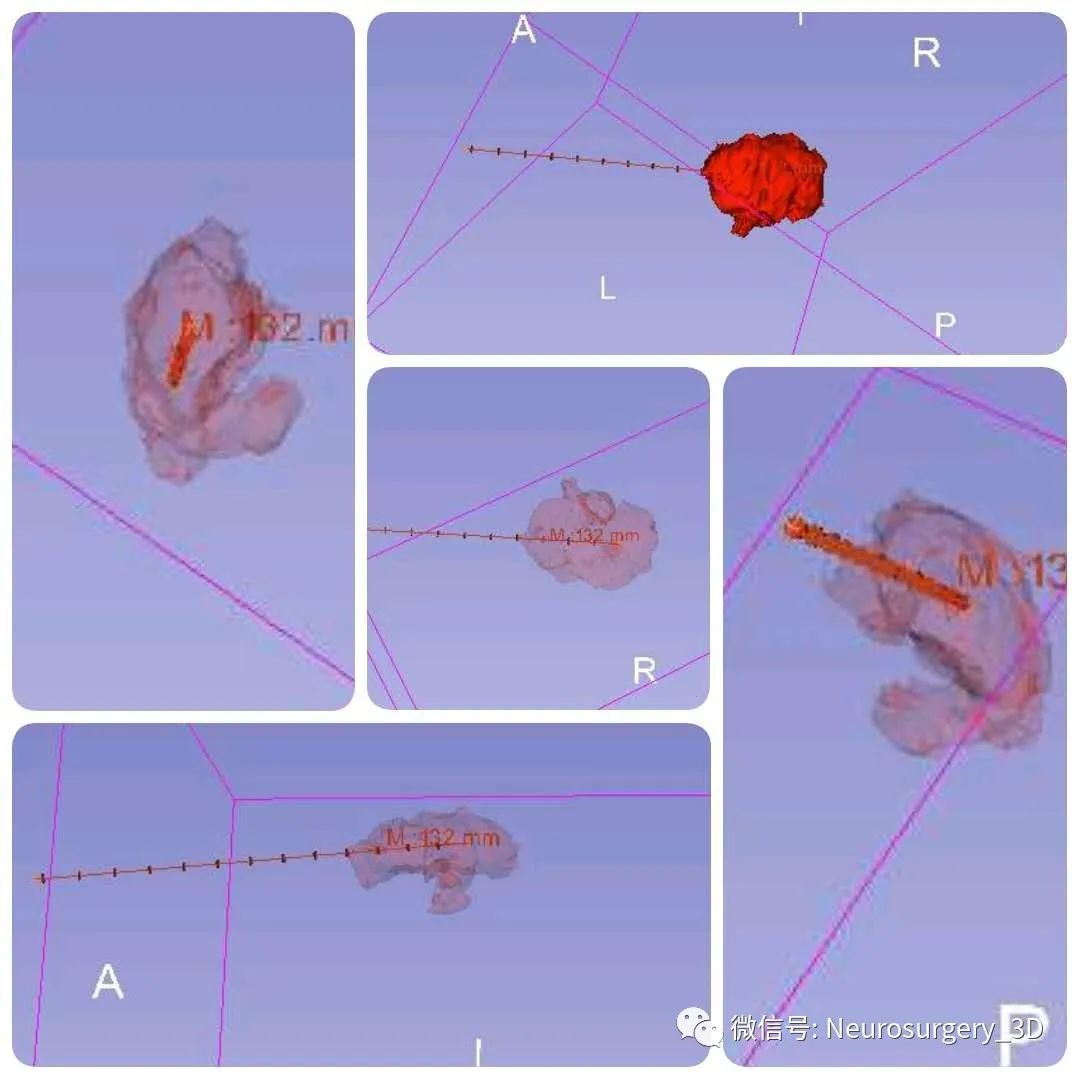

1、利用Ruler测量出穿刺血肿靶点至穿刺外口的距离,并设计出穿刺路径顺血肿长轴走形在血肿中心(并非如下图所示所有穿刺路径均与矢状面平行、请注意穿刺深度),避开颅内重要结构如额窦、上矢状窦等。

透视化血肿状态下显示穿刺路径走形在血肿中心

2、建立穿刺导管

3、生成空管